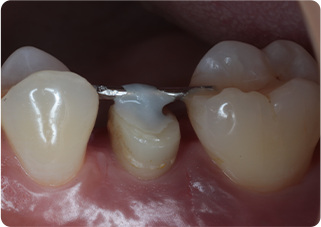

矯正的挺出・歯冠長延長術・セラミッククラウン症例①

術前

MTM、歯冠長延長後

術後

| 主訴 | むし歯の歯を抜きたくない |

|---|---|

| 治療期間/回数 | 5ヵ月、10回 |

| 価格(税込) | 154,000円(税込) |

| リスク・副作用 | セラミックの破損・脱離が生じる場合がある |

| ポイント | 通常だと抜歯と診断されるが、局所矯正と外科処置を行い、歯根を持ち上げることで、被せ物が可能になった。歯根を持ち上げたことにより長期的に安定した被せ物が可能になる。 |